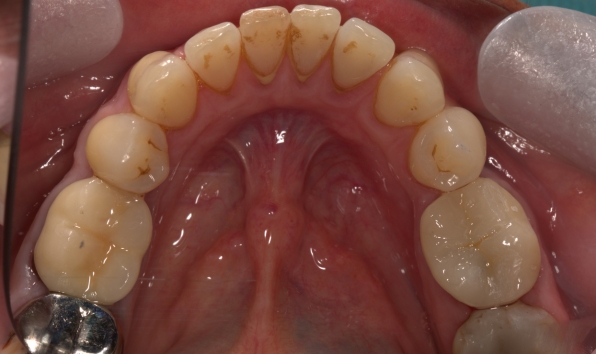

Onlay - case 1 before Before

Onlay - case 1 after After

Onlay - case 1